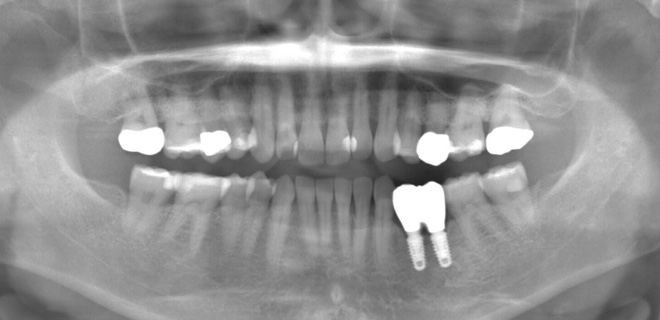

高畑先生が製作したインプラント上部構造(セラミック歯)の治療例

治療前の口腔内写真

全体的な噛み合わせが狂っている状態でした。

全顎治療(フルマウス治療)で理想的な噛み合わせを再建していきます。

治療中のデジタルデータ

治療後のレントゲン写真

治療後の口腔内写真

患者様は50代女性、治療期間は1年。

この症例の治療費

奥歯スタンダードインプラント4本→1,760,000円(税込)

《インプラント1本あたり440,000円(税込)》

セラミック20本→2,640,000円(税込)

《セラミック1本あたり132,000円(税込)》

咬合再構成(全ての仮歯と噛み合わせ治療)→792,000円(税込)

総額5,192,000円(税込)

この症例のリスク

治療中の仮歯が外れたり壊れたりすることがあります。

インプラントが稀に脱落することがあります。

セラミックが稀に欠けたり割れたりする可能性があります。